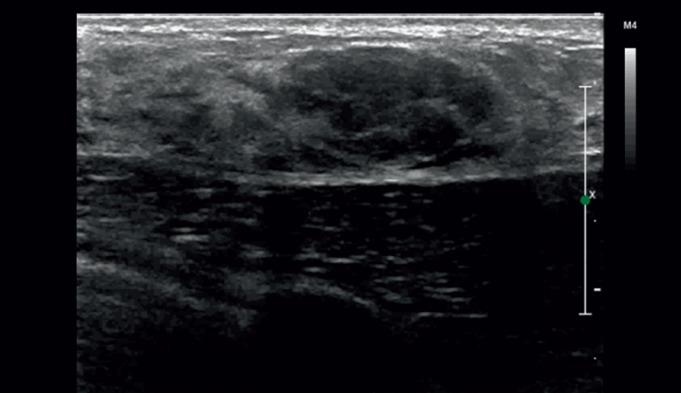

Recent years have witnessed a dynamic development of mammary gland imaging techniques, particularly ultrasonography and magnetic resonance imaging. A challenge related to these studies is the increase in the precision of the anatomical assessment of breast, particularly for early detection of subclinical lesions, performance of ultrasound- guided biopsy procedures, and accurate preoperative location of pathological lesions so as to optimize the surgical treatment. Ultrasound imaging is a primary and baseline diagnostic procedure the patient with suspected pathological lesions within breast is referred to by the surgeon. Lesions visualized in ultrasound scans are classified according to the BI-RADS US assessment categories. The successive categories (2 through 6) encompass individual pathological lesions, estimating the risk of malignancy and provide guidelines for further diagnostic and therapeutic management. This article described the important aspects of ultrasonographic imaging of focal lesions within the breasts as significant from the standpoint of surgical treatment of patients falling within BI-RADS US categories 3, 4, 5, and 6. Attention is drawn to the importance of ultrasound scans in the assessment of axillary fossa lymph nodes before the decision regarding the surgical treatment.